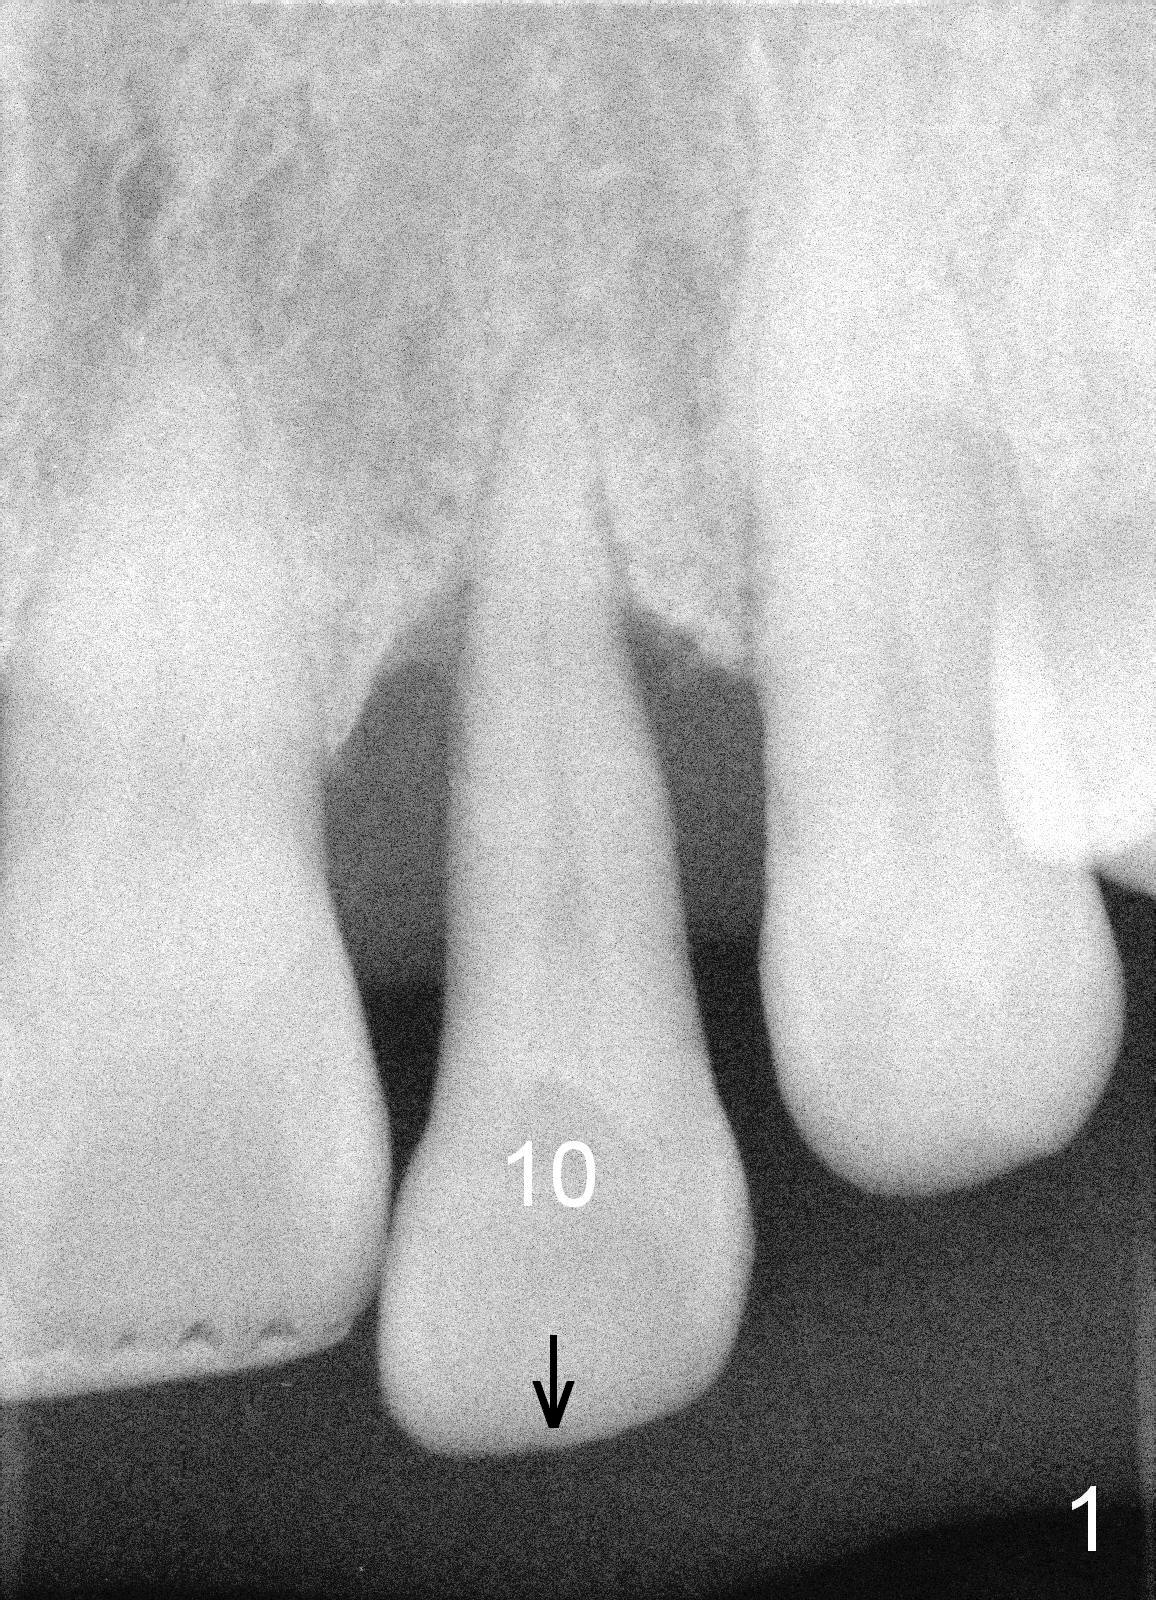

A 46-year-old lady has severe chronic periodontitis. The tooth #10 has drifted inferiorly and labially (Fig.1). One month and a half after #31 immediate implant, she wants to take care of #10. After extraction, measure the socket and tooth dimension. The implant (green box in Fig.2) diameter should be at least 2 mm smaller than the buccopalatal width of the socket. The platform of the implant should be 2-3 mm superior to the CEJ (cementoenamel junction (arrowheads)) of the neighboring teeth. The exposed implant threads will be covered by bone graft (red circles). Since the gingiva is thick (coronoapically), the abutment (gold color) cuff is expected to be 3-4 mm.

If the labial gingiva is thick (buccopalatally), a cemented abutment is chosen to support an immediate provisional. Otherwise, a temporary abutment will be used. It is reported that the temporary abutment promotes gingival growth. Which abutment is chosen?